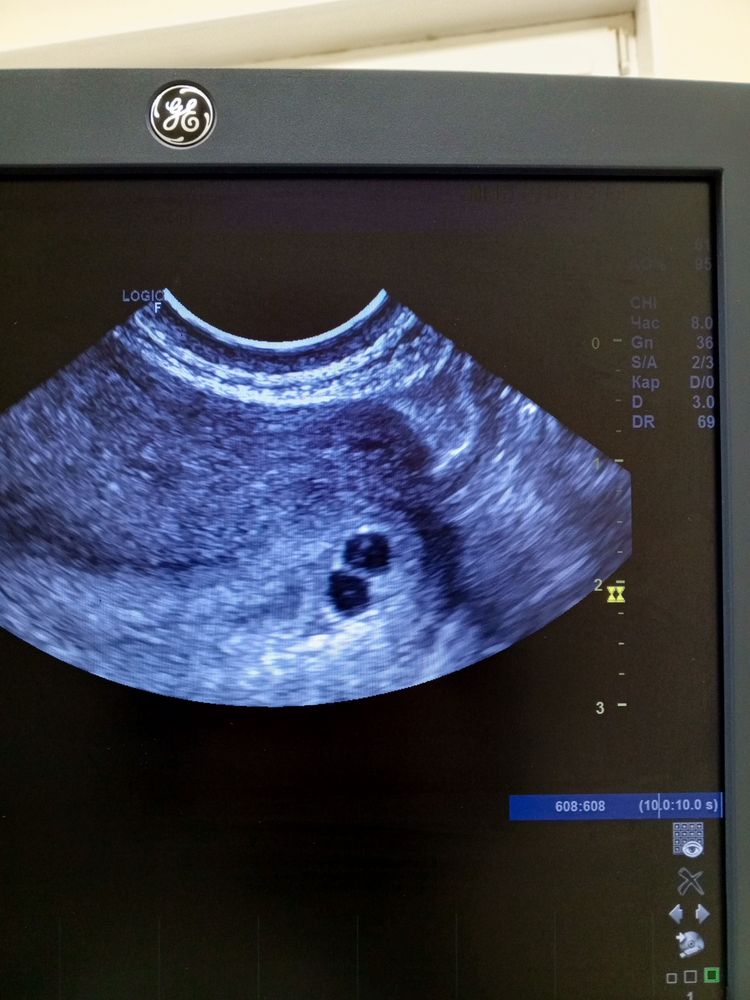

Ну что, вот и сходили на УЗИ)

Алевтина, по ХГЧ вообще непонятно. 21-740, 23-1380, 26-1840. Ставили замершую. Сегодня контрольное УЗИ. В шоке все,включая узиста и врача, как такое может быть. ХГЧ и для одного маленький, а тут два, ещё и с желточными мешочками, ещё и в одном уже есть эмбрион. Вот такое чудо бывает, оказывается

Просто ради интереса: специалист говорит, что развитие соответствует сроку, тогда вопрос: в начале указано срок беременности 5 недель, а ПЯ соответствуют 3м неделям. 🤔или это потому что их 2 сразу? Пока аккуратно за Вас порадуюсь, пусть все хорошо будет

Ирина, 5 недель по месячным, а 3 - по эмбриональному

Мышонок, в шоке,что два! Три дня назад не могли ни одного найти🤣